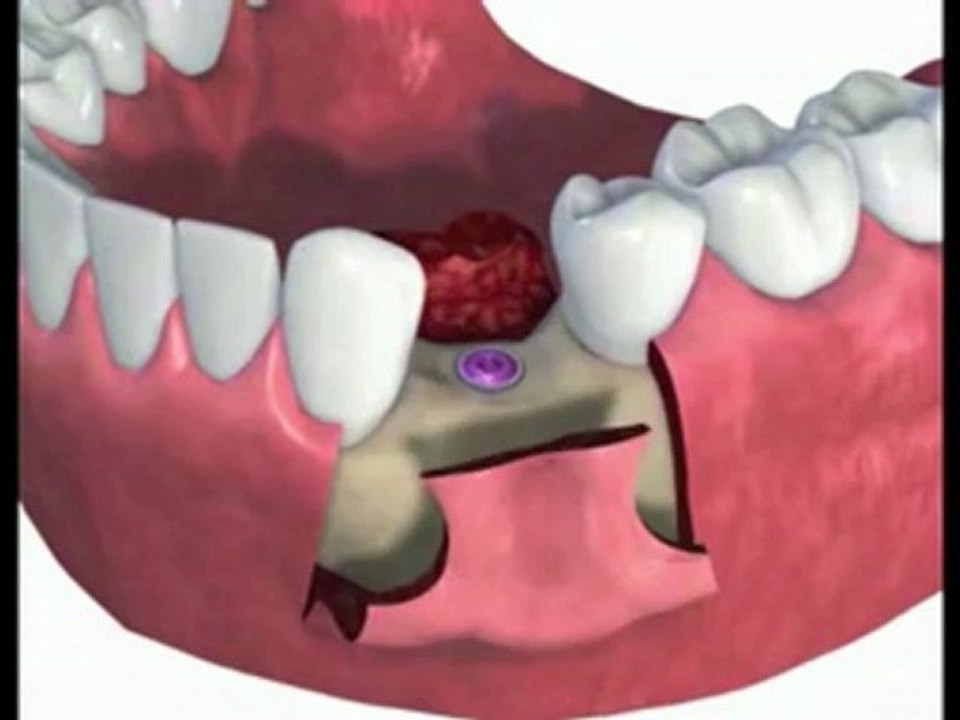

Dental Implant - Real Time Computer Guided Implant Placement - IGI Webinar